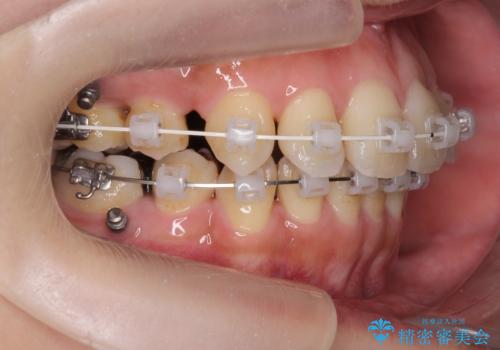

八重歯を矯正治療で治したい!

- 八重歯・がたつきのある歯並びの改善を求めて来院されました。

全部の歯が入り切るスペースがなかったため、小臼歯4本を抜去しワイヤーを用いたマルチブラケット矯正を選択しました。

歯並びの改善と共に、歯ブラシがしやすくなった!と喜んでいただくことができました。